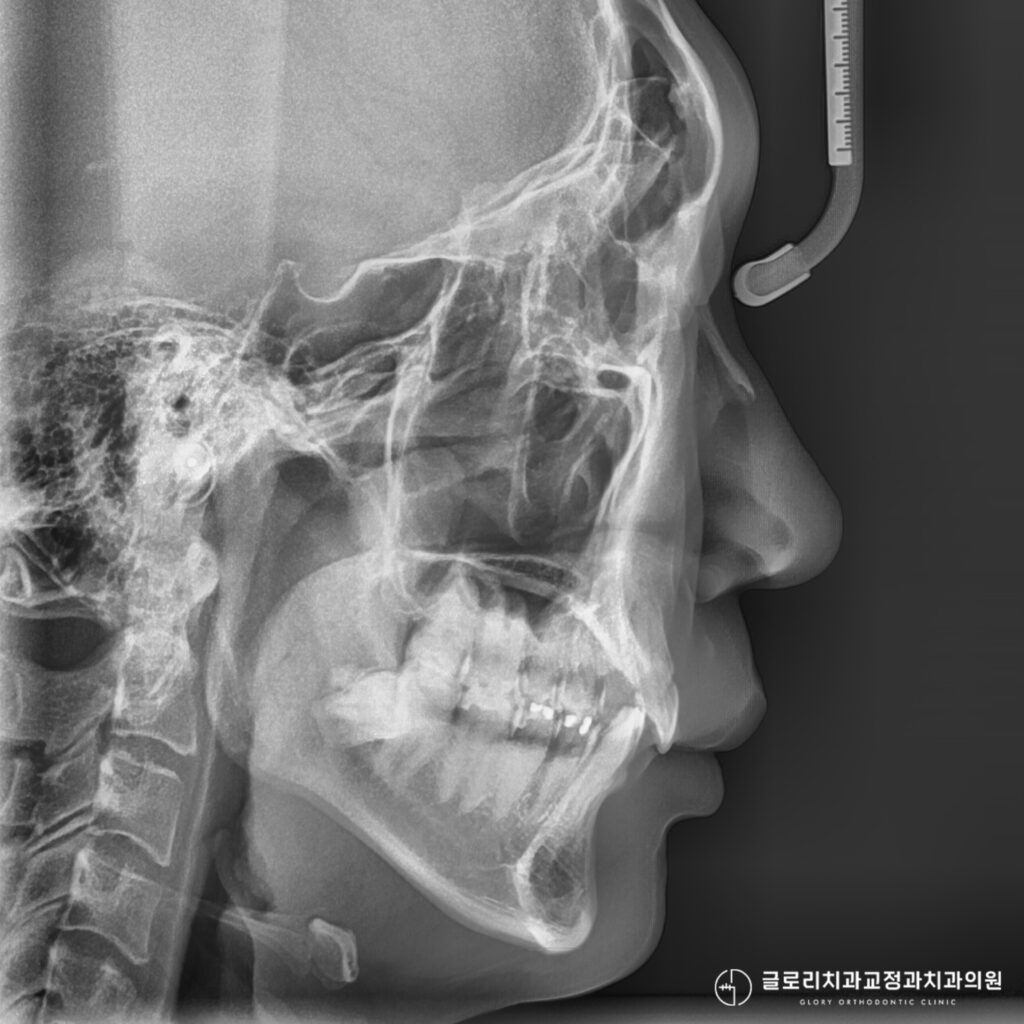

과개교합의 원인은 선천적 요인과 후천적 요인으로 나눌 수 있습니다.

선천적으로는 위턱이 과도하게 발달하거나, 반대로 아래턱의 성장이 부족한 경우에 나타납니다.

골격적인 불균형이 원인인 경우에는 성장기에 적절한 개입이 필요할 수 있습니다.

중랑구 교정치과 인비절라인 치료 기간은 개인의 교합 상태와 치아 이동량에 따라 달라집니다.

정확한 진단을 위해서는 구강 검진과 정밀 분석이 선행되어야 합니다.

엑스레이 촬영과 구강 스캔을 통해 현재 상태를 파악하고, 적합한 치료 계획을 수립합니다.